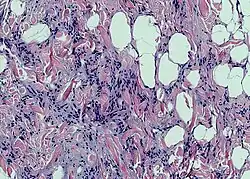

У новорождённых детей и некоторых животных (грызунов и животных, впадающих в спячку) выражена бурая жировая ткань. Адипоциты бурой жировой ткани, по сравнению с клетками белой жировой ткани, имеют больше митохондрий и вместо одной крупной жировой капли содержат множество мелких жировых включений в цитоплазме (такие адипоциты называют мультилокулярными[6]). Бурый цвет обеспечивается железосодержащими пигментами цитохромами, расположенными в митохондриях. Изменения бурой жировой ткани при голодании выражены меньше, чем белой[7].